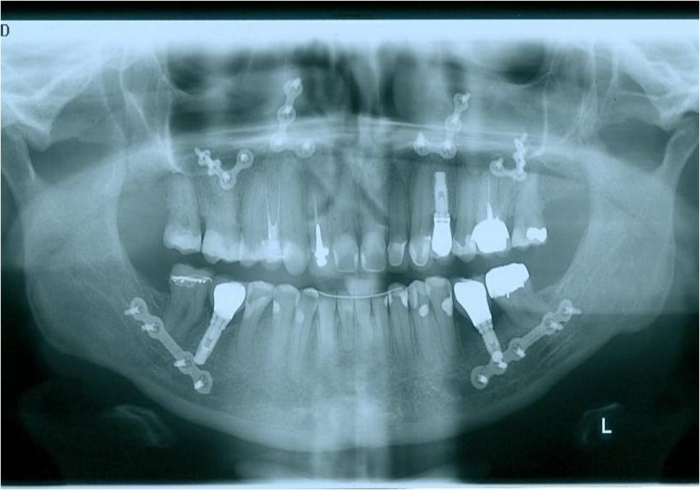

Raio x panorâmico inicial

Raio x panorâmico final